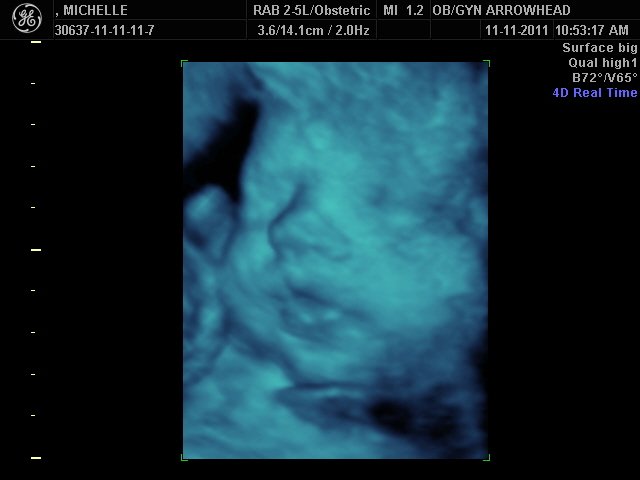

We offer complimentary 3D/4D Ultrasounds to all our OB patients around 30 weeks! The following photos are some examples of our work, shown with permission from our patients.